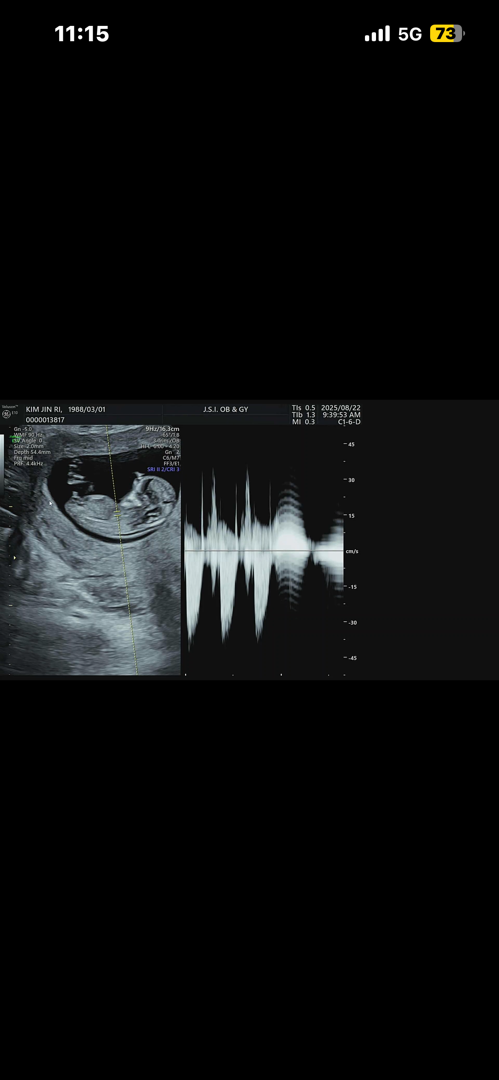

이정도면 아들맞죠?ㅠㅜ

아들확정인거죠? 하하하하하 전.....벌써 아들이 둘이나있는데 말이져 ㅋㅋㅋㅋㅋㅋㅋㅋㅋㅋㅋ 그저 웃음만 나오네요 ㅋㅋㅋ 누구 아니라고 말해줄사람 없나요오오오오😂

오웃ㅋㅋㅋㅋㅋㅋㅋㅋㅋㅋㅋ!!!각도법도 확신은 없지만...너무 ㅅ...닼ㅋㅋㅋ

저도 각도법1도모르는데 그냥막 알겟죠 ㅋㅋㅋㅋㅋㅋㅋㅋㅋㅋㅋㅋ